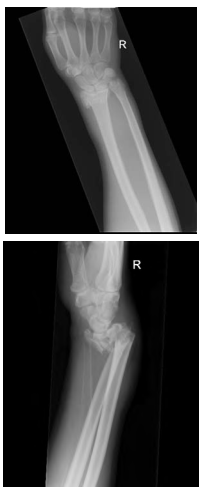

Uma paciente idosa apresentou episódio de vertigem rotatória e caiu com o punho fletido. No exame físico, apresenta deformidade importante de punho, edema e dor limitante.

Com base nesse caso clínico e nas imagens de radiografia apresentadas, é correto afirmar que se trata de uma fratura de